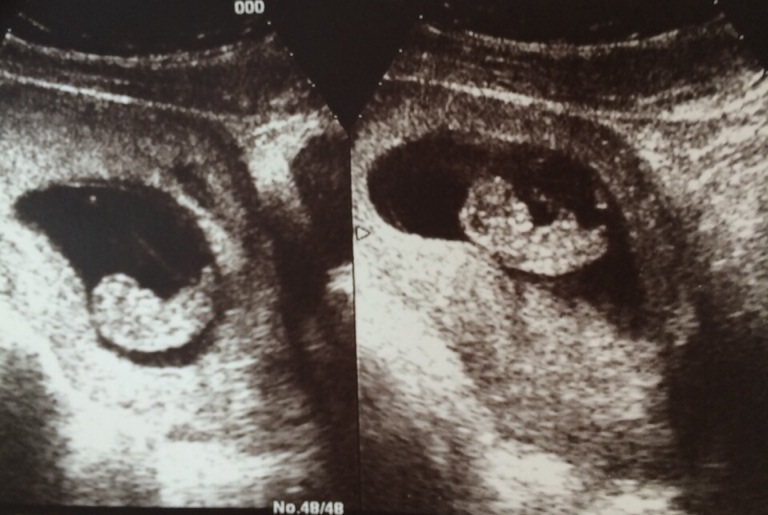

Скрининг мы прошли еще две недели назад, у нас всё отлично! Малыши махали мне ручками и выглядели бодрыми :) Узистка сказала что на мальчиков похожи )))

Ну и закончу на позитивной ноте фоткой наших малышей :)